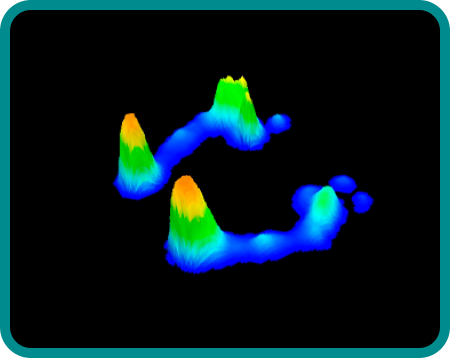

Baropodometria

(teste da pisada)

Serão avaliados os pontos de maior pressão no pé, tipo de pé, tipo de pisada e descarga de peso durante a marcha.